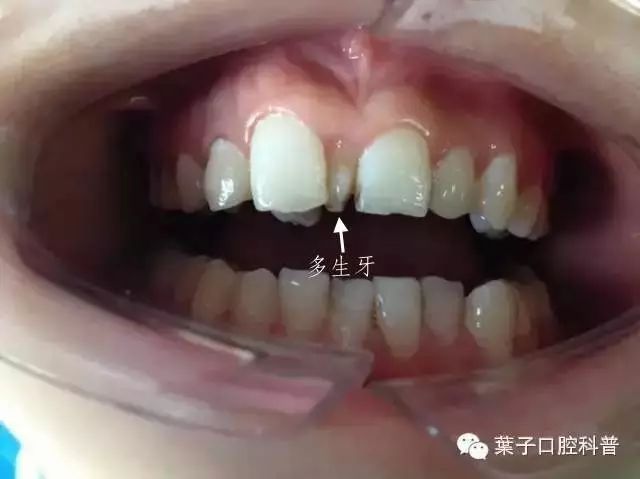

多生牙 —— 顾名思义,就是多余长出来的牙齿,最常见的是上颌“正中多生牙”,也就是长在门牙之间的牙齿。

一般来说,单侧或对称都有可能生长,有的已经萌出,有的会埋伏阻生,有的甚至会倒着长。多生牙一般是小锥形,牙根较短。

多生牙的典型外形

案例中小姑娘的多生牙是属于埋伏生长。还有一种情况是,“长出来”了的多生牙。

这是一位刚开始换牙的小朋友,新换出来的牙齿特别小,而且是锥形的。家长还以为是门牙形状畸形,带着来医院检查,才发现原来这是多生牙。